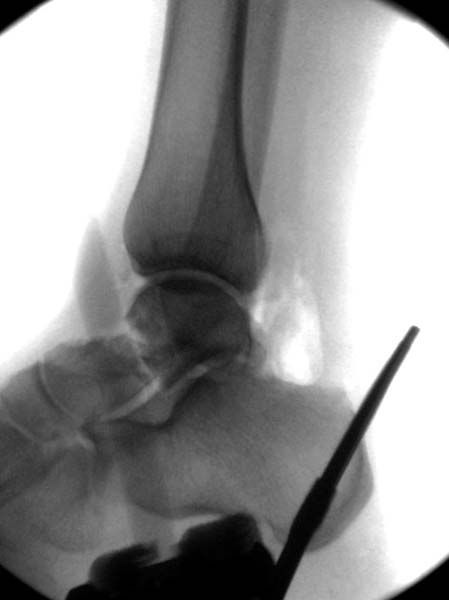

> Больная стабильная после хирургических мероприятии и получив добро,

> приступили к закрытому вправлению таранной кости с укладкой наружного

> фиксатора. Затем укладка больную на бок и открытый остеосинтез

> После спадения отека на стопе произведена фиксация тарана. Кстати, коллеги

> пересмотрели первоначальную консультацию по позвоночнику и на двух уровнях